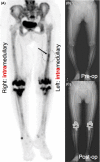

NaF PET assessment of bone metabolic changes around the femoral canal by intramedullary femoral alignment technique in total knee arthroplasty

We used the NaF PET scan to assess osteometabolic changes around the distal half of the femoral canal by intramedullary (IM) drill for femoral IM guiding rod insertion in total knee arthroplasty. Gentle IM rod insertion and focused attention can minimize surgical stress-induced biological reaction of the femoral IM canal.